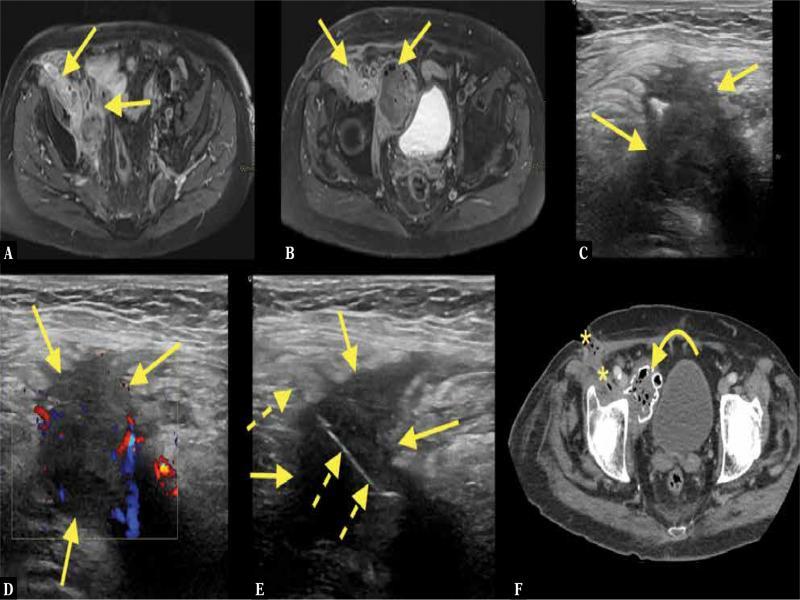

Fig. 10.

A 20-year-old football player with pain in the thoracic spine. The patient was referred for spinal MRI, where a solid tumor with calcifications was revealed on the left side of Th12 ( A–C, E ; straight arrow – tumor). CT without intravenous contrast ( D, F ) showed calcifications both in the center and periphery of the lesion, which in combination with the patient’s pain was worrisome. The differential diagnosis included myositis ossificans, osteosarcoma, and osteoblastoma. US-CNB was performed ( G–I ; dashed arrows – biopsy needle). The final histopathological diagnosis of osteoblastoma was made on a repeated US-CNB